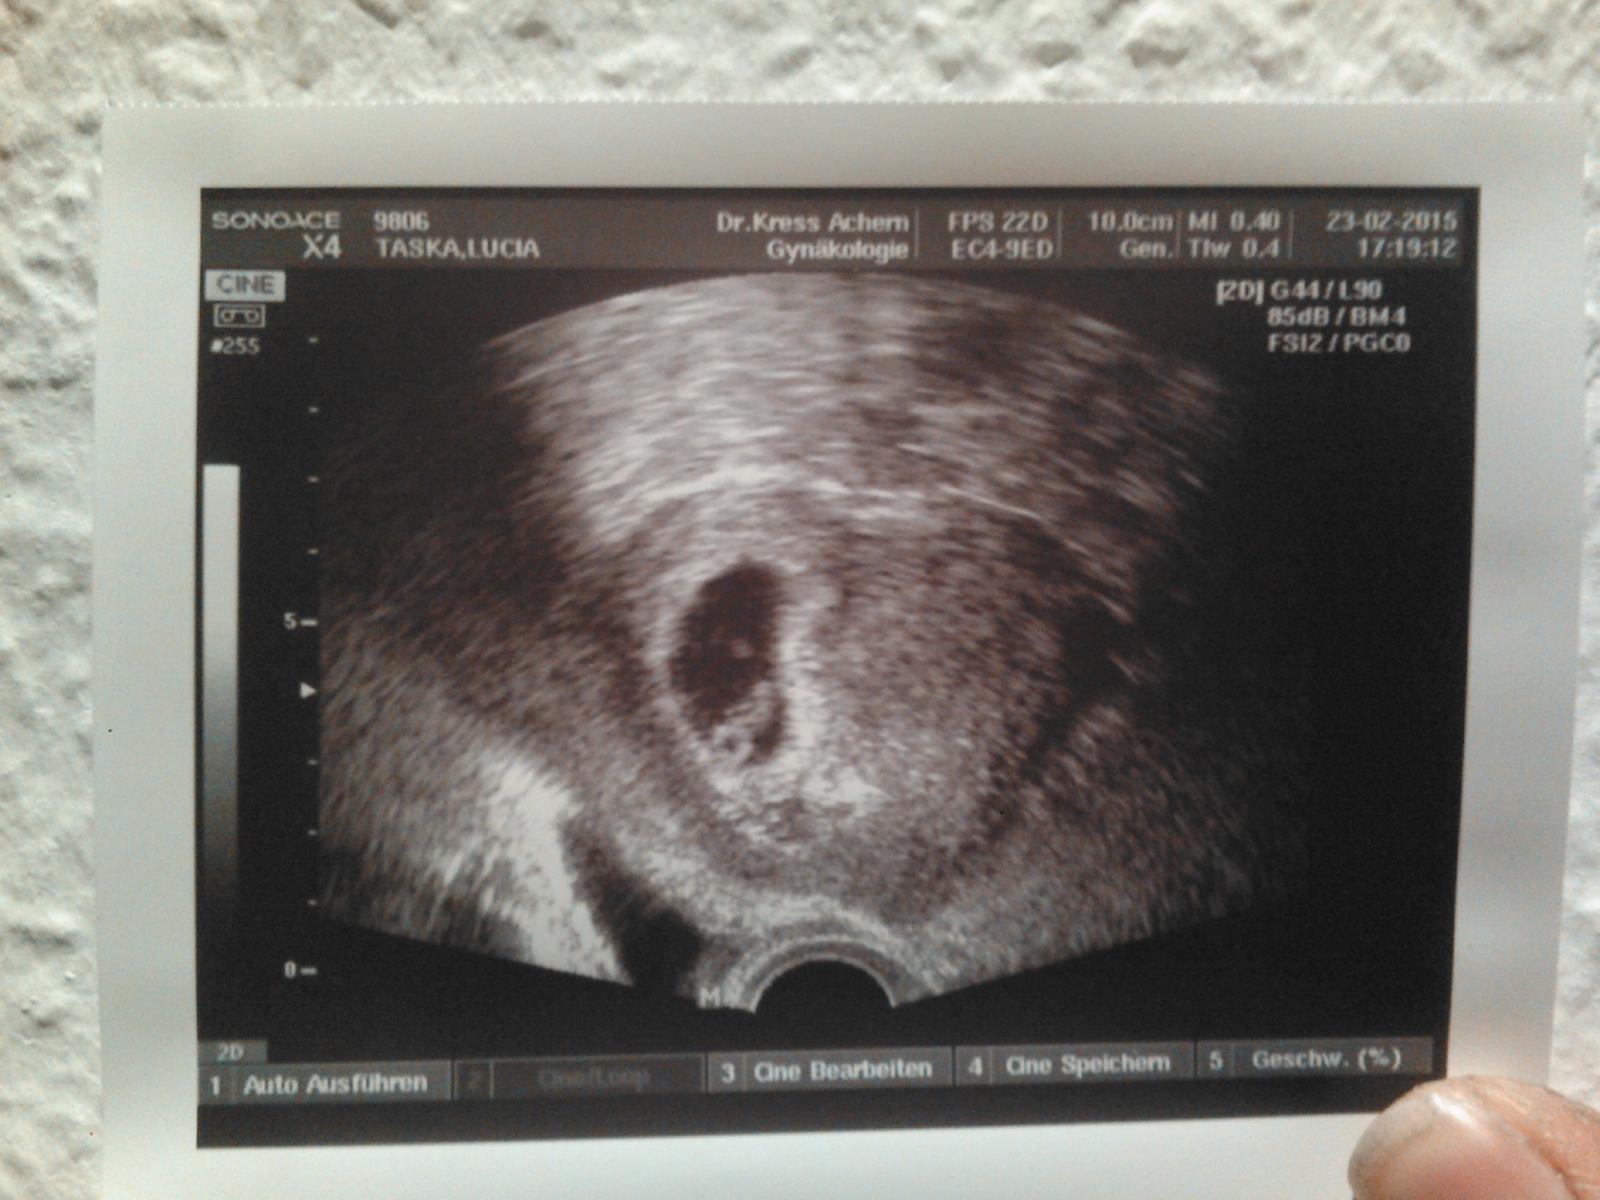

Tehulky chcem sa opýtať kedy bolo na ultrazvuku už vidno bábätko 👶 ako sa to počítaju vlastne tie týždne 🙂 🤰❤😍🙏

@kacenaaa http://tehotenstvo.academy.sk tu to vies krasne vyratat. Ja som mala 6+1tt prve sono a bolo babo aj so srdieckom. Ale o chvilu sa tu zapoja take, ktore budu tvrdit, ze skor ako 8tt nechod, lebo ked ony nemali potvrdene srdiecko, tak ani ty nebudes mat 😉